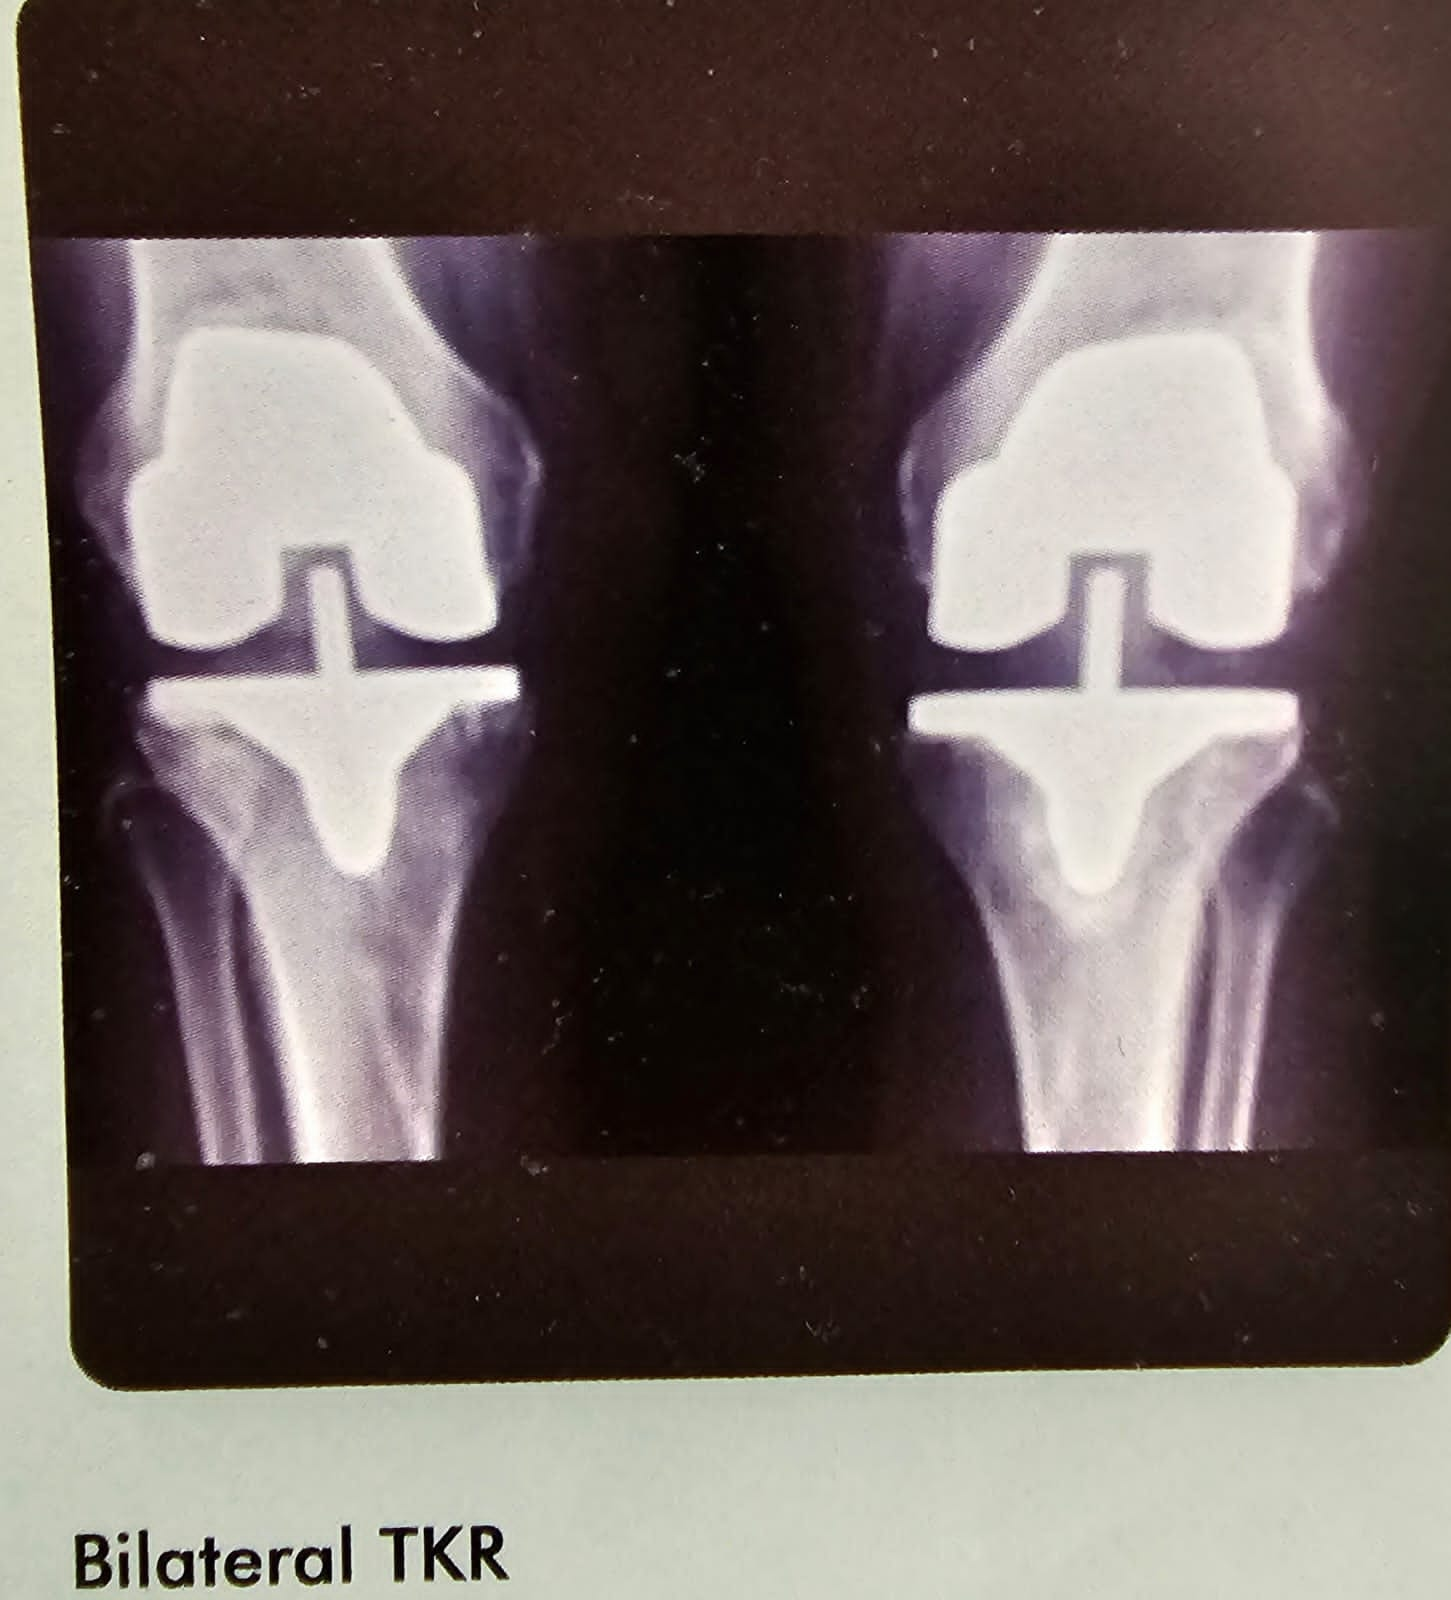

Bilateral TKR

This is a X ray of bilateral total knee replacement of a 60 year old. Which was did under one anesthetic.